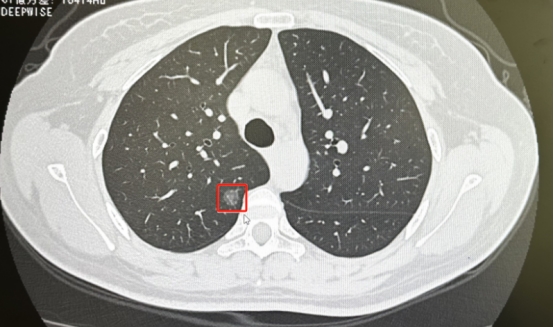

国家呼吸医学中心团队再创新!女性早期肺癌有望“无管无痕”化

不少朋友发现,自己身边不吸烟的女性亲友发现肺结节的越来越多,而且不乏非常年轻的女性朋友。尽管随着外科技术的发展,可以实现单孔“无管”化快速康复治疗,但毕竟还是会留下一个小于3厘米的小切口,对爱美的女性来说,依然是种“灾害”!

不用插管!肺癌手术,裸眼3D单孔机器人创新实现“无管化”

近期,广州医科大学附属第一医院国家呼吸医学中心何建行教授团队牵头开展一项裸眼3D蛇形臂单孔腔镜手术机器人的临床试验,创新性地将“无管化”技术融入其中,成功为两位患者在自主呼吸麻醉下完成肺癌根治手术,引领单孔机器人手术在胸科领域迈上新高度。